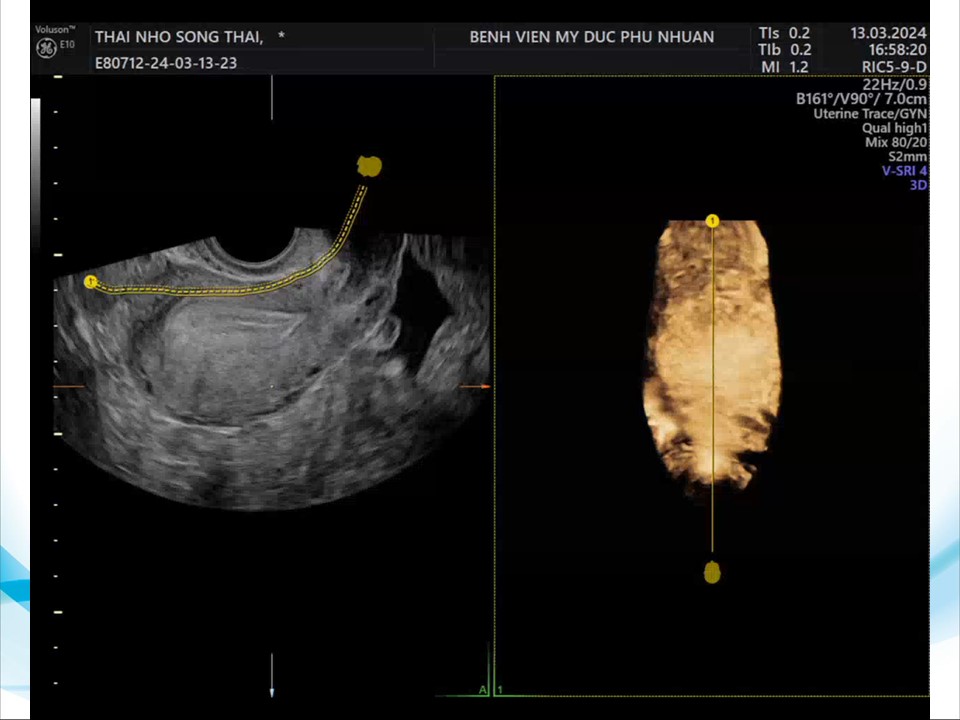

Siêu âm đánh giá khả năng sống của thai giai đoạn sớm

BS. CKI Phạm Thị Phương Anh - BV Mỹ Đức